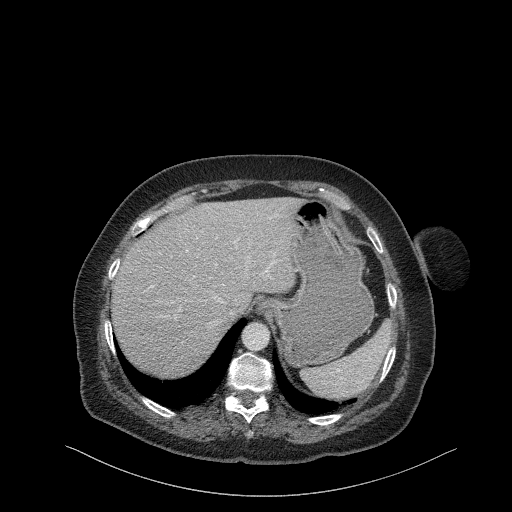

Generated VENOUS CT scan (A→B translation)

Full window (WL 1023.5, WW 4095 β†’ Low βˆ’1024, High +3071)

Lung window (WL -600, WW 1500 β†’ Low βˆ’1350, High +150)

Mediastinum window (WL 40, WW 400 β†’ Low βˆ’160, High +240)